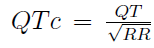

Intrakardiální EKG je grafický záznam srdeční elektrické aktivity, jenž je snímán pomocí do srdce zavedených katétrů. V tabulce 1.1 jsou uvedeny délky základních intervalů na intrakardiálním EKG při sinusovém rytmu.

Vysvětlení tabulky 1.1: PA interval je doba od počátku P vny na povrchovém EKG po 1. výchylku zaznamenanou z katétru umístěného na Hisovu svazku, tento interval podává informaci o intraatriálním vedení. AH, HV intervaly, jenž jsou zobrazeny na obrázku

1.2, se měří na intrakardiálním EKG při sinusovém rytmu pro vyhodnocení AV převodu. AH interval se měří mezi potenciálem síní a potenciálem Hisova svazku, HV interval mezi potenciálem Hisova svazku a potenciálem komor. Potenciály snímané intrakardiál-ním EKG z oblasti Hisova svazku jsou označovány zkratkou HBE. QRS je délka QRS komplexu a QTc je korekční QT interval, jedná se o QT interval s korekcí na tepovou frekvenci:

V praxi se používá spíše QTc než QT, protože není ovliňován RR srdeční frekvencí. S výskytem delších QTc intervalů stoupá pravděpodobnost výskytu maligní komorové tachykardie. [4, 22, 31]